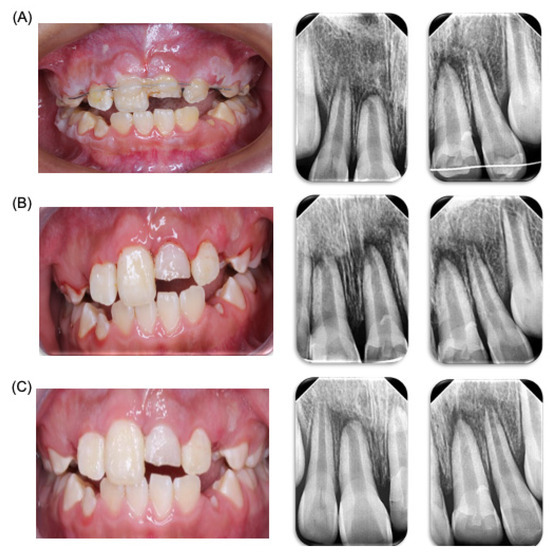

Figure 2.

Dental trauma follow-up. Control and clinic and radiologic follow-up of patient. (A) Clinic and radiological revision one week after accident. (B) Clinic and radiological revision two weeks after the accident. (C) Clinic and radiological revision due to the new trauma.

A control appointment was scheduled for one week later, with a follow-up for splint removal in two weeks. In the third week, the patient was referred to an endodontist (Clinic of Endodontics, Endodontics Postgraduate Program, Faculty of Dentistry, Autonomous University of San Luis Potosi, SLP, Mexico) for vitality tests. At the follow-up appointment, the patient was asymptomatic but exhibited poor oral hygiene with generalized dental plaque. Instructions were given for the modified Bass brushing technique with a soft-bristled brush. Sutures were removed, periapical radiographs were taken, and the patient was advised to continue with a soft diet. One week later, the patient returned for another control appointment. He was symptom-free and showed improved hygiene. The brushing technique was reinforced, the splint was removed without complications, and additional periapical radiographs were taken. The patient was then referred to the endodontist for further evaluation (Figure 2). Four days later, the patient returned to the pediatric stomatology clinic, reporting additional trauma from a classmate hitting him on the upper anterior teeth. A panoramic X-ray was taken for evaluation. During the physical examination, no new alterations were observed, so continued observation was recommended (Figure 2).